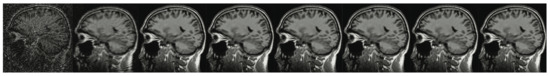

Figure 6. A brain imaging example. From left to right: A: Image reconstructed from partially sampled PROPELLER blade, B:Cartesian sampling grid without image registration applied (with no downsampling applied), C: B-spline Cubic interpolation, D: Non-Rigid Multi-Modal 3D Medical Image Registration Based on Foveated Modality Independent Neighbourhood Descriptor [45], E: Enhanced deep residual networks for single image super-resolution [14], F: Image super-resolution using very deep residual channel attention networks [16], G: Residual dense network for image super-resolution [15], H: super-resolution with proposed sampling scheme and motion compensation (the proposed algorithm). Compression ratio is 50%. Please see Table 1 for the PSNR values at other compression ratios.